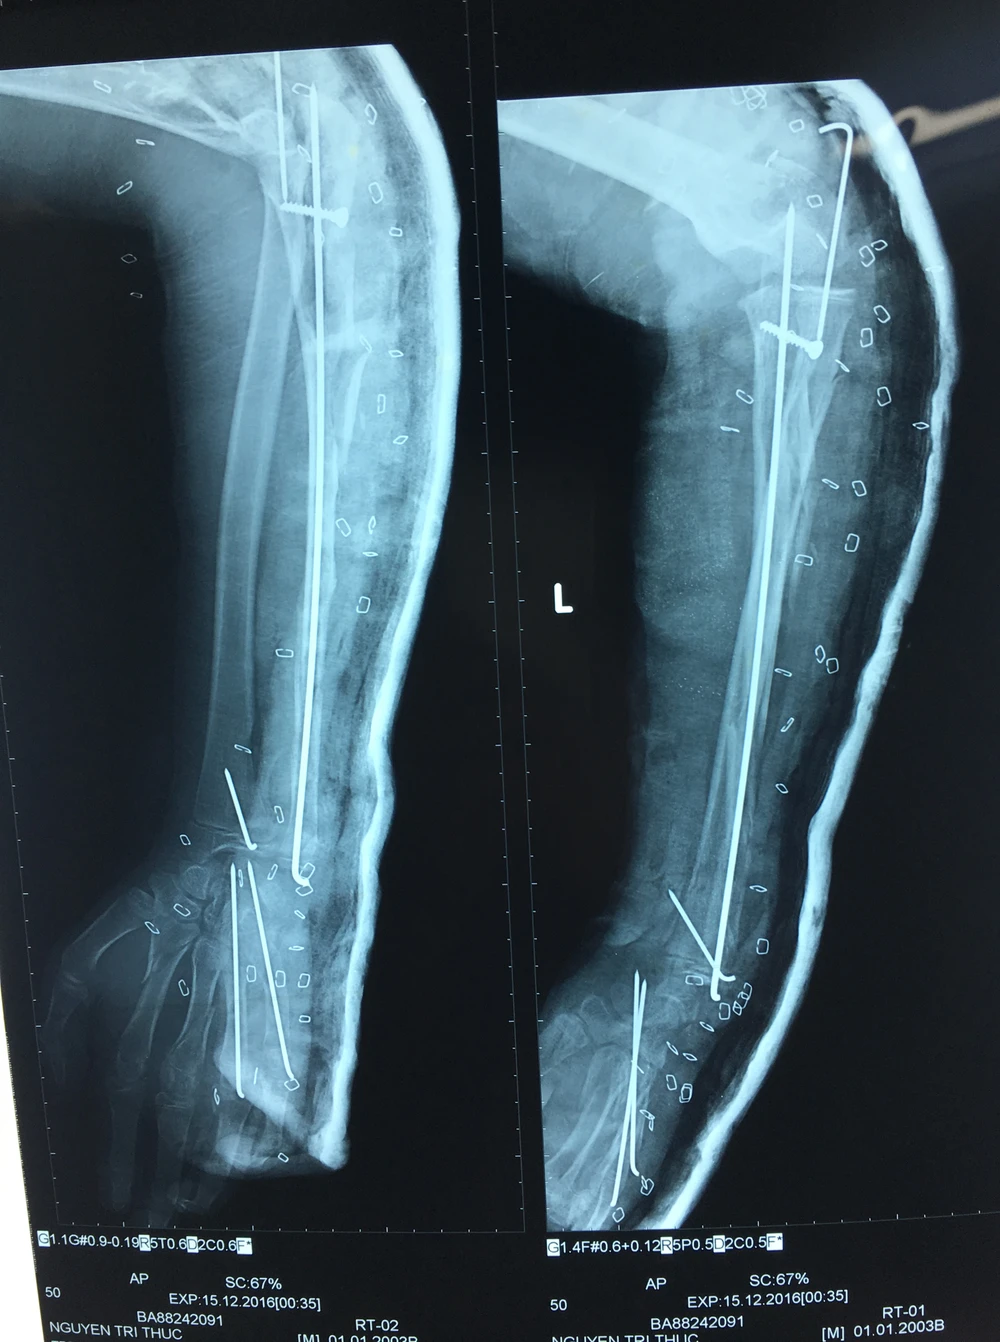

Kết quả chụp X-quang cho thấy xương tay trái của bệnh nhi T. bị gãy rất nhiều. Ảnh: VÕ KHÁNH

Chưa hết, bệnh nhi còn bị đứt nhiều tầng cơ tam đầu, dập đứt nhiều tầng toàn bộ cơ mặt sau cẳng tay. Bệnh nhi còn bị gãy nhiều tầng xương trụ, trật chỏm quay, gãy xương thuyền, xương cả, xương bàn ngón 4 và 5 tay trái. Người nhà cho biết bệnh nhi đi ghe rớt ngã xuống sông, chân vịt ghe máy cắt vào cẳng tay trái.